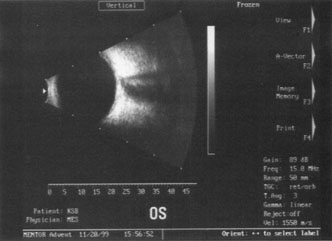

further tests guide the ophthalmologist in planning the surgery. SPECIAL MEASUREMENTS OF VISION Preoperative measurement of vision is meant to determine the patient's current state of visual function. Snellen acuity is routinely tested on all patients as part of their preoperative evaluation. This usually is performed by having the patient read a standardized chart in a darkened room. Although the Snellen acuity scale is the most ubiquitous measure of vision, it measures only one tiny aspect of visual function. Many patients may be profoundly functionally impaired by their degree of visual disability, yet may test surprisingly well measuring Snellen acuity in a darkened room. In these cases, it is incumbent on the ophthalmologist to seek to better understand and document the patient's problems by performing additional testing. Many patients are most bothered by cataract-induced glare. For these patients, acuity testing under glare situations is indicated. There are several methods to assess visual acuity reduction by glare. The choice of method is often best dictated by the patient's history. If a patient complains of glare problems in the supermarket, or other uniformly illuminated environment, the brightness acuity test can be performed (Mentor Ophthalmics). For this test, the specially illuminated handpiece is held in front of the tested eye using best spectacle correction (Fig. 1). The Snellen acuity is rechecked and can be recorded on each of three light settings. Patients who complain of glare from point sources of light, such as oncoming headlights or bright sunshine, may be best evaluated by a different form of glare testing. To simulate the environment of the patients' symptoms, Snellen acuity is measured while directing a point source of light obliquely toward the eye outside their best spectacle correction or outside of a phoropter dialed in with their best manifest refraction (Fig. 2). Still other patients' problems may center on difficulty with reading, seeing street signs, or distinguishing fine patterns. In these individuals, the complaints are related more to contrast; therefore, contrast testing is most appropriate. There are a number of ways to assess the effect of contrast on vision. Regan's sine wave gradients have been used frequently for research purposes and are available in some settings. Various commercial devices are now available to measure visual acuity in different contrast settings and each has its relative merits and detractions. The authors have found the Baylor Visual Acuity Tester (BVAT) monitor (Mentor Ophthalmics) testing of contrast to correlate well with patients' complaints and its simplicity is appealing to both patients and technical staff. In rare instances, patients' complaints may be primarily related to distinguishing colors. Although patients frequently remark about their dramatic improvement in color perception after cataract surgery, there are no convenient methods to document diminished color perception preoperatively. This underscores the importance of correlating patients' complaints with the biomicroscopic examination and the degree of nuclear color change. PROGNOSTIC TESTS Physicians often order special tests to help determine a patient's visual potential. Some of these tests are acuity specific. These can be particularly helpful in guiding patients who may have comorbid ocular conditions. Some devices have been designed to project a Snellen chart through the clearest area of the cataractous lens to assess retinal acuity potential such as the potential acuity meter. Studies also have shown a good predictive value by checking vision with a brightly illuminated near card.53 Of course, this can be performed with no additional office equipment. Various other commercial devices, including interferometry and various different pinhole and illumination device combinations, are available. These approaches are not possible for patients with mature cataracts. Some more general, nonspecific prognostic tests can be performed. If a patient is able to identify the colors of projected lights, this usually indicates that some cone-mediated macular function is present. Blue field endoscopy also may indicate some macular function. This test is performed by projecting a blue light into the eye. The patient may report seeing small round specks moving around in the vision. These specks correspond to white blood cells passing through the perifoveal capillaries. The Purkinje phenomenon is tested easily by rapidly wiggling a transilluminator directed toward the globe through the lower lid in a darkened room. If the patient reports a pattern of crooked lines or branches, then he or she is seeing the shadows cast by the retinal blood vessels, indicating that the posterior pole is attached and functioning to at least some degree. Although positive results from the test are encouraging, some patients may still have limited vision after surgery; similarly, some rare patients may test negatively on all these tests and still recover good vision. Diagnostic Studies Several diagnostic studies provide information that supplements the historical and clinical data obtained by the surgeon. This information enables proper preoperative patient consultation and surgical planning. This section outlines many preoperative tests used for cataract patients. A-SCAN BIOMETRY. Accurate axial length measurement is critical to determine the correct power of the implant lens for the desired refractive result. A-scan biometry is imperative in any patient undergoing cataract surgery. Both contact (applanation) and immersion varieties of A-scan ultrasound units are commercially available. With applanation biometry, a hand-held or slit-lamp mounted probe is gently touched to the corneal surface along the visual axis. Contact A-scans are user dependent and sometimes the authors adjust the surgeon-specific IOL A-constant depending on which ultrasonographer has performed the scan. Nonetheless, outstanding refractive outcomes have been achieved, and the authors have been satisfied with the contact applanation technique. With an immersion probe, a water bath around the eye acts as the medium to conduct sound waves. Although there is no direct contact of the probe with the globe, the water and water bath must, of course, remain in contact with the ocular surface and periorbita. Immersion scans may reduce interobserver variations but are less comfortable and less convenient for patients. A-scan biometry is particularly challenging in eyes containing an oil fill. In this instance laser biometry is still able to achieve excellent measures. LASER PARTIAL COHERENCE OPTICAL BIOMETRY. Although ultrasound requires continuous contact with media that conduct sound waves, laser light passes easily through any clear media, including air, making this a truly noncontact or “no touch” test. Furthermore, the speed of light is not appreciably different in the clear media of the eye and thus excellent, reliable measures can be achieved in eyes containing intraocular lenses, regardless of type and eyes with oil fills within the vitreous cavity. Although some calculation adjustments can be made depending on the pseudophakic status, the differences among implant material are not appreciable different from a practical clinical perspective. Currently, the only commercially available laser biometry device is the IOLMaster (Zeiss). The measurements obtained by the IOLMaster device are extremely reliable, reproducible, and seem to be relatively technician- and observer-independent.54,55This device also can measure keratometry, optical anterior chamber depth measurements, and “white-to-white” measurements in an automated fashion. Because it relies on the passage of laser light through the ocular media, this instrument is unable to obtain measurements in cases where the media prevent laser light passage; for example, white cataracts, axial posterior subcapsular cataracts, or corneal scarring. B-SCAN ULTRASOUND. A mature cataract precludes visualization of the fundus. A B-scan ultrasonographic examination provides a real-time, two-dimensional (2D), cross-sectional image of the globe along the marked axis of the probe (Fig. 3). Cataracts are more common in patients with chronic retinal detachment, prior trauma, or intraocular tumors; therefore, a B-scan study is helpful in excluding structural posterior segment pathology before surgery on a mature cataract. Although a negative result to B-scan evaluation is reassuring, the surgeon should remember that it does not predict postoperative visual outcome. The B-scan can be thought of as a picture of Cincinnati from an airplane; the office buildings may all be standing, but you cannot tell whether the people in them are working.